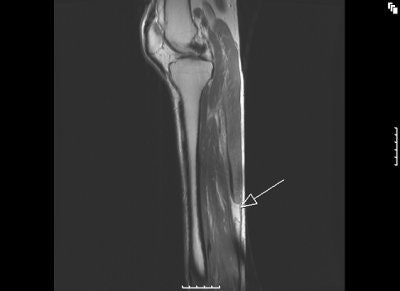

MR images of the tennis leg injury sustained by Mintz. Above, a coronal fat-suppressed image through the back of the calf with the arrow pointing to the muscle tear. The hematoma is tracking up the leg. Below, sagittal MR of the whole calf. Arrow points to the muscle tear and the white below it is the gap from the muscle retraction. Images courtesy of Dr. Douglas Mintz.

![]() |